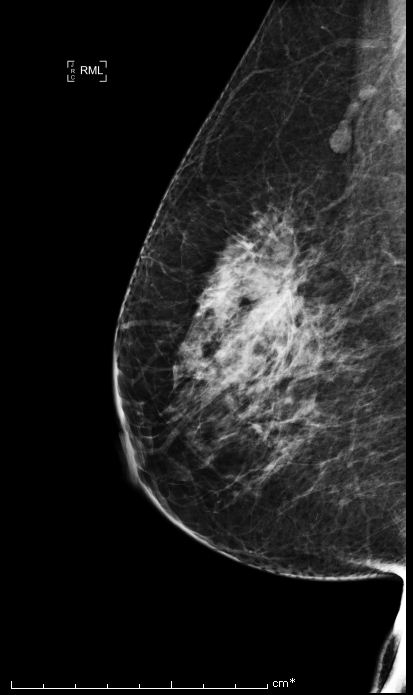

Bi-rads 4 means that the findings on the image are suspicious and that there is an approximately 20 percent to 35 percent chance that a breast cancer is present.

We proceed to calculate the volume of the tumor contained in the breast from the following Bi-rads 4 breast images.

Similarly, we use the same algorithm to evaluate the tumor volume for 4 Bi-rads 4 images and the results are the following:

| Bi-rads 4 Image | Optimal Threshold | Tumor Volume |

|---|---|---|

| Image 1 | 120.574 | 11% of breast volume |

| Image 2 | 59.9143 | 45% of breast volume |

| Image 3 | 239.696 | 0.24% of breast volume |

| Image 4 | 244.590 | 0.0287% of breast volume |